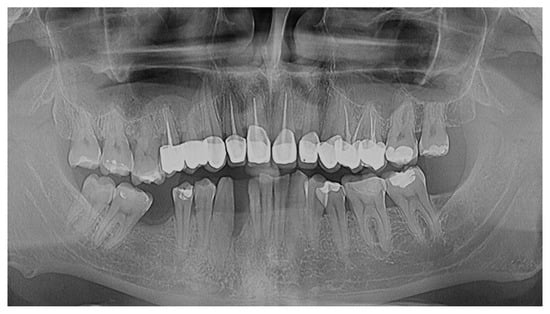

2.5. Six-Month Follow-Up and Evaluations